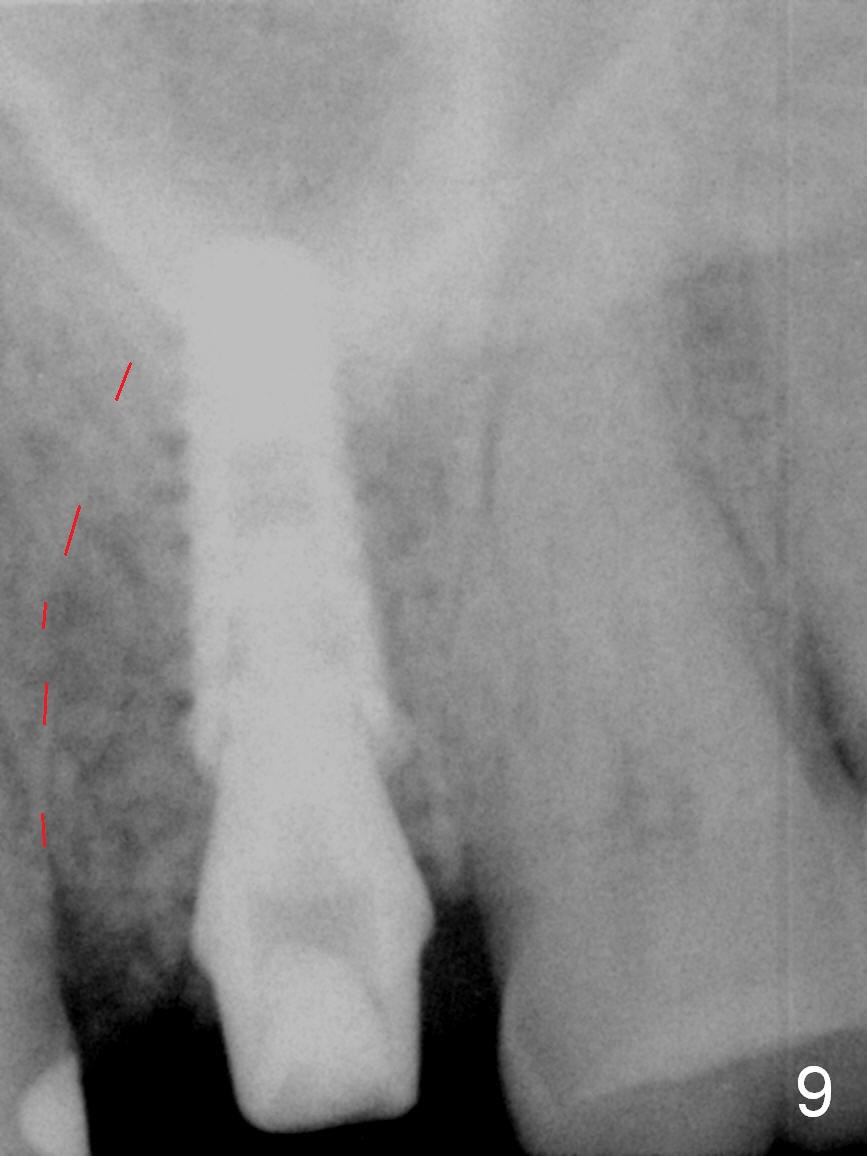

The septal bone is dense and the osteotomy is enlarged by alternating use of drills and expanders. By the time 3.8 mm ME is tapped in (Fig.6), the buccal plate of the septum is perforated. The ME is stable, in spite of the fact that it is only supported by 2-3 mm bone buccally (Fig.7). Continuously alternating use of MEs and drills leads to placement of a 5x11 mm implant with 30 Ncm insertion torque and sinus lift. After placement of bone graft (Fig.8 *) and 5x4(3) mm pair abutment (A), an immediate provisional is fabricated. Red dashed lines in Fig.6,9 represent the mesial outline of the socket, whereas black dashed in Fig.6 sinus floor. It suggests that the implant is stabilized by relatively small amount of native bone. Although IBS implants have aggressive thread patterns, a proper apical osteotomy should be prepared in the depth (perforates the sinus floor in this case) and diameter (4.3 mm drill) prior to placement.